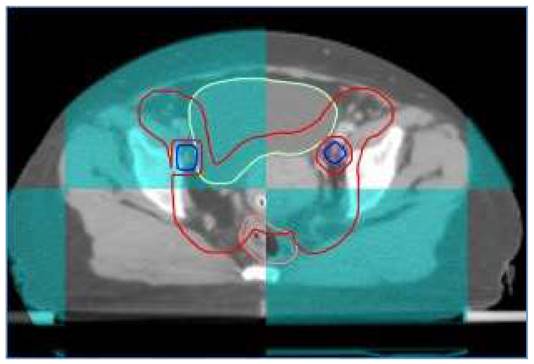

At our institute, image guide radiotherapy (IGRT) was routinely performed for patients with cervical cancer receiving definitive IMRT. For patients treated with FF-IMRT and VMAT, weekly cone beam compute tomography (CBCT) was performed. Daily on-board megavoltage CT (MVCT) was conducted for patients receiving HT every day before treatment (shown in Figure 1).

Figure 1

A patient with FIGO IIIC1 cervical cancer treated with IG-IMRT (Cone beam CT).